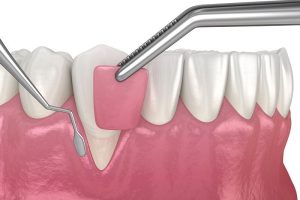

Мягкотканная пластика

Мягкотканная пластика – это процедура, направленная на восстановление или улучшение состояния десны вокруг имплантов.

Она может потребоваться для создания эстетичного контура десны или устранения рецессии (обнажения шеек зубов).

Современные методики и материалы позволяют добиться естественного внешнего вида и улучшить гигиенические условия.

Цифровые технологии помогают точно спланировать вмешательство и достичь гармоничного результата. Мягкотканная пластика часто выполняется вместе с другими видами имплантации для достижения максимальной эстетики.